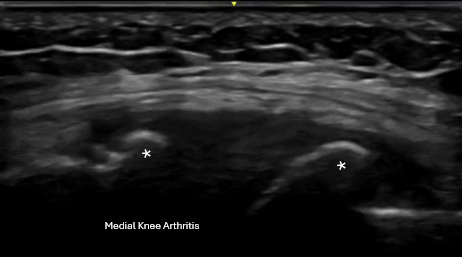

What We Commonly See on Knee Ultrasound

Using real-time musculoskeletal ultrasound, we commonly evaluate for:

• Arthritis

Ultrasound allows us to visualize the tendon and surrounding structures, perform dynamic exams, and compare findings to the opposite side when needed.

Real-time musculoskeletal ultrasound image showing arthritis of the knee